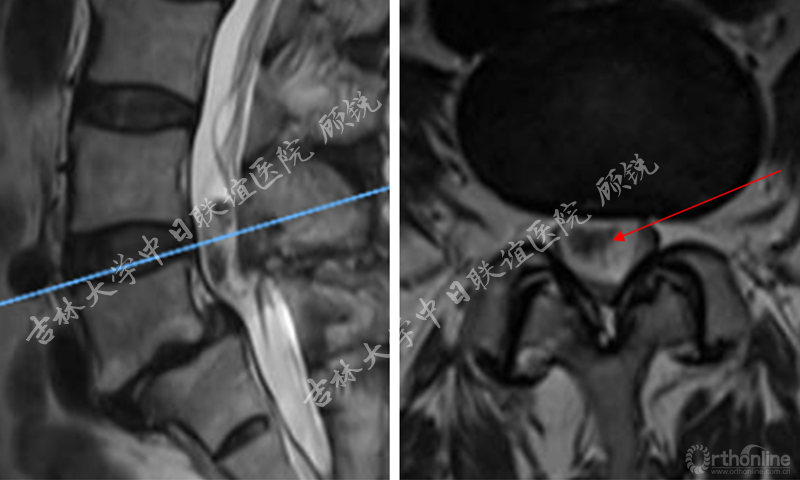

增强MRI增强如下:

腰椎增强MRI示:

占位组织强化明显为实质病变,依据瘤体与硬膜间呈锐角;T1W1:等信号;T2W1:混杂高信号STIR:环状增强,Non-enhancement area(+)。经科内会诊该患者的诊断为:峡部裂型腰椎滑脱(L5 Ⅱ度)、腰椎管内占位性病变(神经鞘瘤?)。Ozawa H, Aizawa T, Kanno H.Epidemiology of surgically treated primary spinal cord tumors in Miyagi, Japan.Neuroepidemiology. 2013;41(3-4):156-60

责任病变是峡部裂型腰椎滑脱(L5 II度)。诊断依据:临床思维一元论原则(Unitary theory);患者左侧L5神经根的症状与CT显示左侧L5S1椎间孔狭窄对应;椎管内瘤体主要位于右侧。